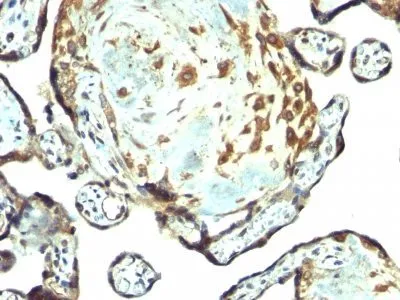

- Applications: IHC, FFPE (verified)

- Validated Applications: IHC, FFPE

- Positive Control: Placenta or breast carcinoma

- Additionnal Information: Immunohistology formalin-fixed 1-2 ug/mL|Staining of formalin-fixed tissues requires boiling tissue sections in 10 mM citrate buffer, pH 6.0, for 10-20 min followed by cooling at RT for 20 minutes|Flow Cytometry 0.5-1 ug/million cells/0.1 mL|Immunofluorescence 1-2 ug/mL|Optimal dilution for a specific application should be determined by user